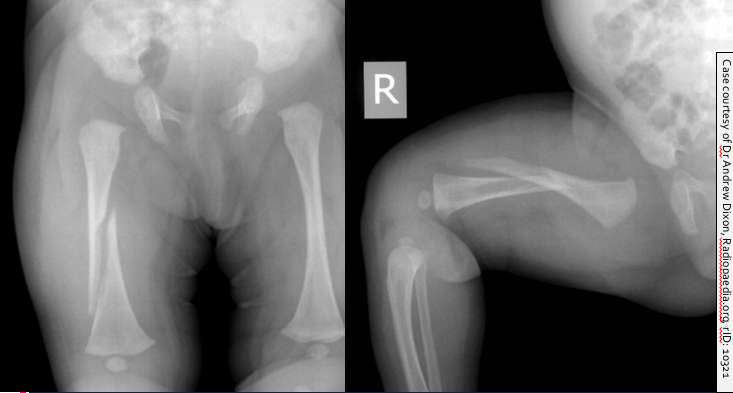

A mother brought her six-week old daughter to the ED. The child had become very irritable after the mother had accidentally twisted the infant’s right leg whilst changing her nappy.

The child was irritable and became distressed when her right leg was examined.

What abnormalities can you see in the X-ray of this child’s lower limb bones?

Can you explain the abnormal appearance?